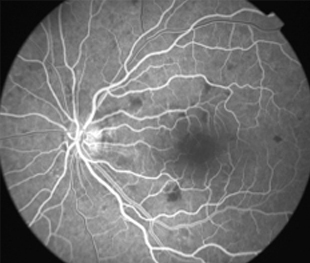

Angiografía OD

Angiografía OI

- Angiografía: teñido arterial, escape capilar, más tardíamente, no perfusion arteriolar y venular con teñido de las paredes vasculares y dilatación venosa.